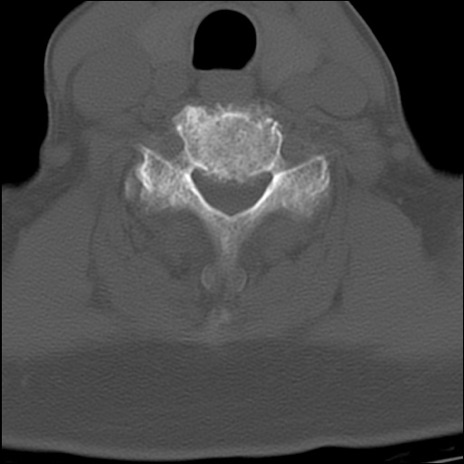

頚椎CT